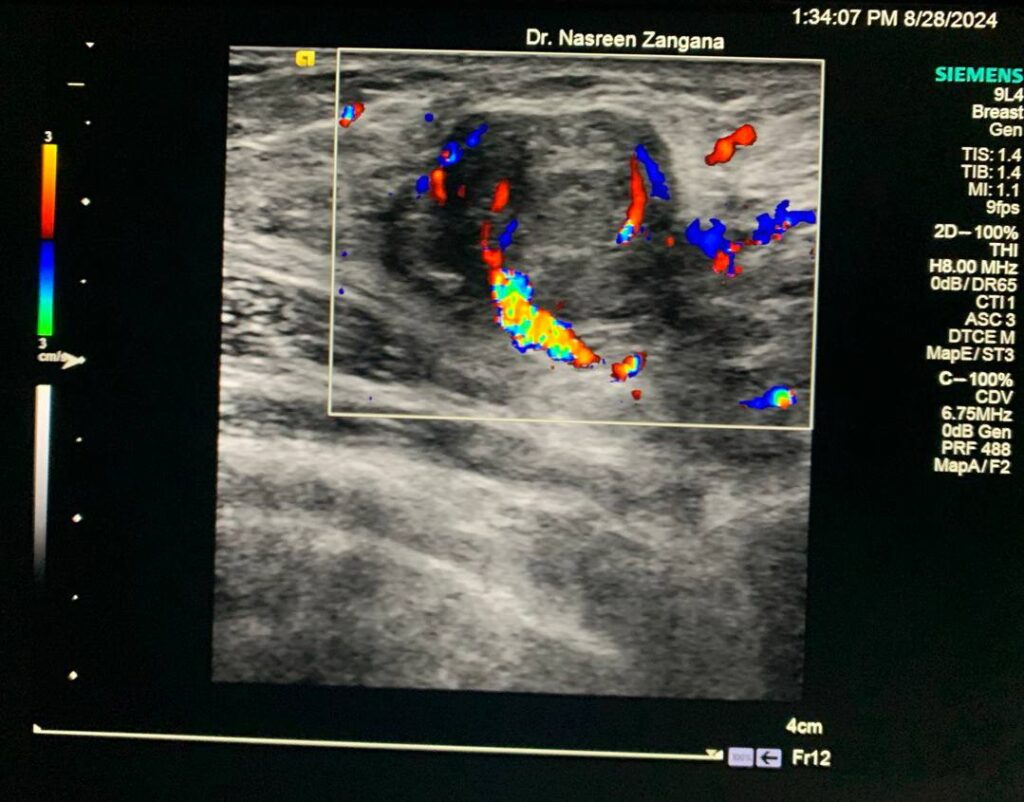

Breast U/S

Hypoechoic vascular solid mass at left axilla ectopic gladular breast tissue of lactating woman, lactating adenoma? fibroadenoma ?